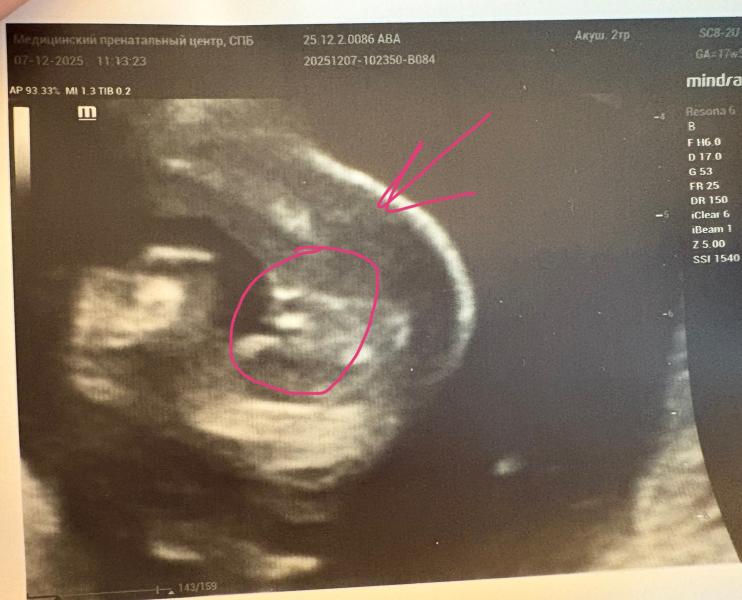

Ходила лицезреть дочь..дочь😵💫До сих пор не верится и не привычно, хоть уже у меня есть 100500 фото женской письки, и кровь по определению пола, но ДОЧЬ🙏🏻😍😭

300 грамм весит моя дама, шейка 36(у меня швы) ттт🙏🏻 Только дчерь стесняшка и категорически отказывалась фоткаться, спасибо хоть фак не показала😂 ну и по традиции после каждого узи(а их тонна) я что то покупаю женщине своей😍

Боже девки, после пяти сыновей подряд видеть на узи что то кроме машонки…бесценно😂

Сегодня была на узи,врач сказал,что похоже на девочку,но потом в конце как то выразился,,но наверное в я ошибаюсь,,, и фото показал,прям как у вас,фото пиписки😁может случится чудо и у нас все таки будет девочка